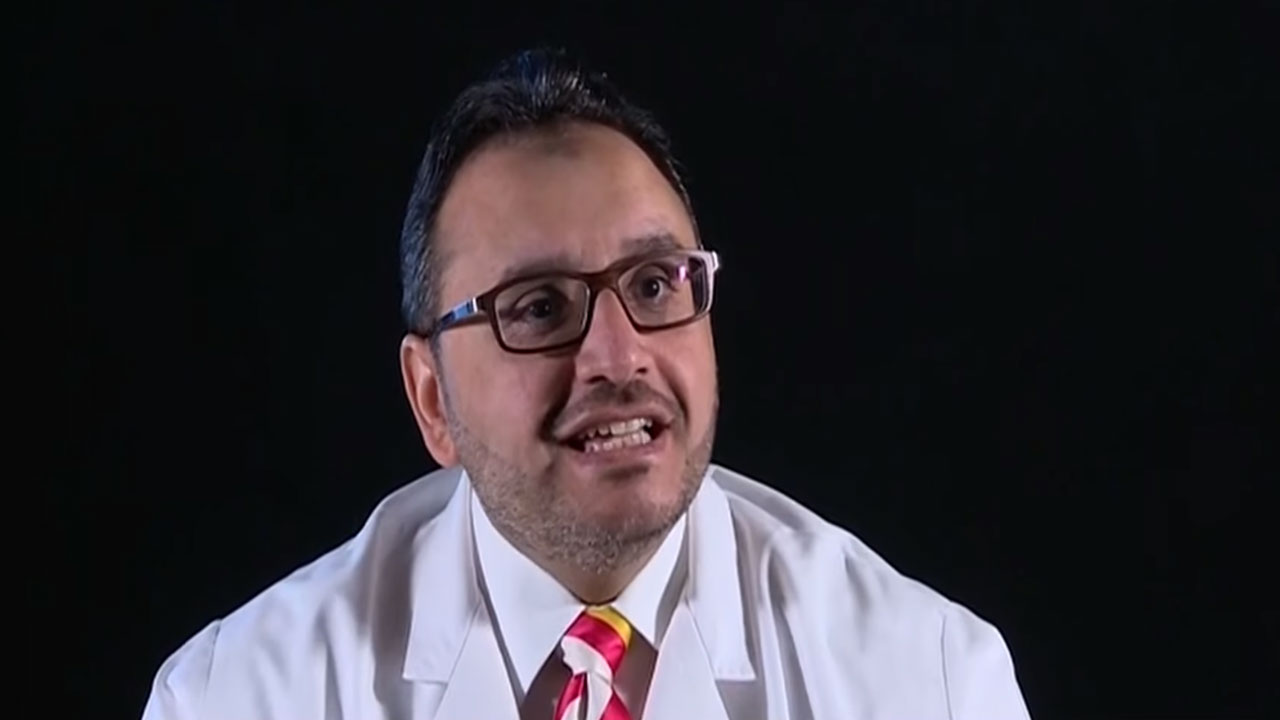

“باهبري” يكشف متى يكون نقص الأكسجين خطر على حياة الشخص